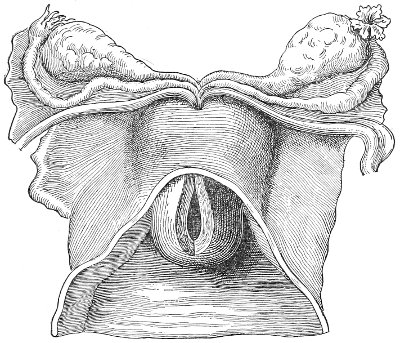

An accurate knowledge of the anatomy and mechanism of the female perineum is essential to an understanding of the nature and treatment of injuries to this structure. The anatomical structures lying between the anus behind and the symphysis pubis in front are those that most directly interest the gynecologist. Proceeding from 57 below upward, we find the following structures lying in superimposed planes: the skin, the superficial fascia, the deep layer of the superficial fascia, the transversus perinæi and the sphincter vaginæ muscles, the anterior layer of the triangular ligament, the posterior layer of the triangular ligament, the levator ani muscle (Fig. 19).

Fig. 18, A.—Superficial structures of the female perineum (Weisse).

Fig. 19.—Dissection of female perineum: on the left side the perineal muscles are exposed by the reflection of the perineal fascia; on the right side the muscles and the superficial layer of the triangular ligament have been removed, thereby exposing the deep layer of the ligament. S. V., Sphincter vaginæ muscle.

The vagina passes through these structures. They surround and support the ostium vaginæ as the fascia and muscles surround and support the opening of the rectum or the anus. The muscles and fasciæ are attached in the median line between the anus and the vagina, and therefore this part of the body, which is called the perineum, is supported or maintained in its 58 proper position by these various structures. The transversus perinæi arises from the ramus of the ischium and is inserted in the perineum. The bulbo-cavernosus, or sphincter vaginæ, arises in the perineum and is inserted in and about the clitoris. The inner fibers of the levator ani arise from the symphysis pubis and are inserted in the perineum and the lower part of the vagina (Fig. 20). When these muscles contract, their action, therefore, is to draw the perineum upward and forward. At the same time the anus is drawn upward and forward, and so also is the posterior margin of the ostium vaginæ and the lower portion of the posterior vaginal wall.

Fig. 20.—Dissection of female perineum, showing the deeper structures after removal of the levator and sphincter ani muscles.

The vagina has no circular sphincter like the anus, but 59 the vaginal month is kept closed by the action of the transversus perinæi, sphincter vaginæ, and levator ani muscles, which draw the perineum forward, and thus keep the posterior vaginal wall in apposition with the anterior wall.

Fig. 21.—Muscular floor of the pelvis seen from above.

This sling of muscles and fascia, which surrounds and supports the opening of the vagina, may readily be felt in the nulliparous woman by introducing the finger in the vagina and pressing backward and outward toward the ischio-rectal fossa. We then feel plainly, immediately within the ostium vaginæ, a firm resisting band of tissue, apparently about half an inch broad, embracing the posterior portion of the lower vagina. This band is formed by the inner edges of the various muscles and planes of fascia that have been described.

Fig. 22.—Sagittal section showing relations of the several layers of fascia within the pelvic floor (Dickinson).

The vagina extends, as a transverse slit in the pelvic floor, upward and backward, approximately in the direction 60 of a line drawn from the ostium vaginæ to the fifth sacral vertebra. It is approximately parallel with the conjugate of the brim, so that when the woman is erect the long axis of the vagina is inclined at an angle of 60° to the horizon. The vagina is not a vertical open tube: it is a slit in the pelvic floor, in health always closed by the accurate apposition of the anterior and posterior walls (Fig. 21). The anterior vaginal wall is about 2½ inches long in a vertical mesial line. The posterior vaginal wall is about 3½ inches long. The vaginal walls are triangular in shape, being broader above than below. The shape of the normal vagina at the pelvic outlet is shown by Fig. 23. The section here shows the vaginal 61 slit of the shape of the letter H. The portions of the slit extending backward and somewhat outward are called the vaginal sulci or furrows. They are directions of diminished resistance in which tears are liable to occur.

Fig. 23.—Section illustrating the characteristic form of the vaginal cleft (Henle): Ua, urethra; Va, vagina; L, levator ani; R, rectum.] 62